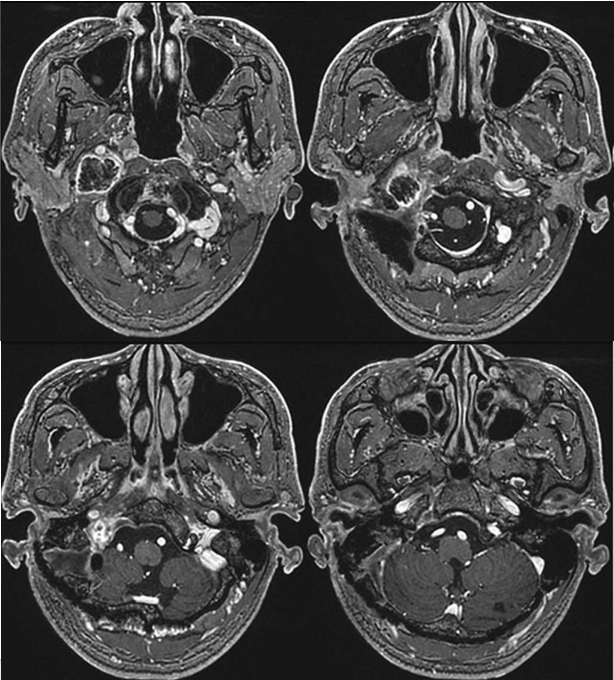

32岁的李先生,就是因为持续声音嘶哑,甚至喝水时容易呛到,一直不见好转才去医院检查。结果发现,他的脑子里长了一个3.7厘米的巨大肿瘤。不仅内部出现了囊性变,还直接压迫到了颈内静脉,并向颅底的颈静脉孔延伸。

术前MRI

考虑到肿瘤体积较大,且内部已出现囊性变化,医生团队认为,相比立体定向放疗,手术切除是更合适的选择。

手术的关键,在于精细分离肿瘤与周围重要的神经和血管——特别是后组颅神经和颈内动脉,必须避免损伤。

好消息是,手术过程顺利,肿瘤被完整切除,原先受压迫的颈内静脉也恢复了正常血流。患者术后颅神经功能保留良好,仅出现轻微暂时性不适,之后也完全恢复正常。复查磁共振显示肿瘤切除彻底,也没有出现新的神经功能问题。